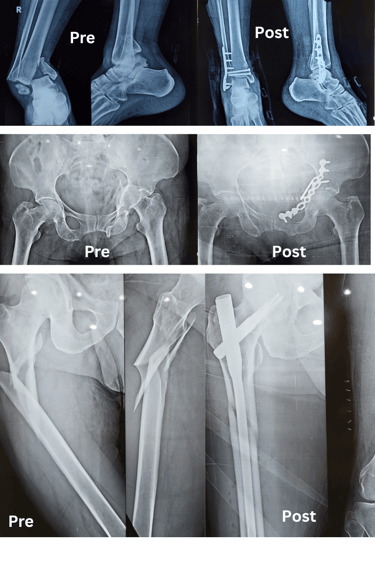

Sivam Hospital – Advanced Trauma Care In Chennai

At Sivam Hospital, we provide 24/7 emergency and trauma care with highly skilled doctors, advanced equipment, and immediate response. Our trauma center specializes in critical injury management, accident care, emergency surgery, and life-saving treatment.

Our expert trauma team provides comprehensive fracture and injury management with advanced techniques and personalized care.

Simple Fractures – Treated effectively with splinting or plaster of paris application 24X7

Compound Fractures – Specialized care to prevent infection and restore function.

Major Fractures – Multimodal treatment to stabilise the patient immediately and team work to stabilise the fractures and other associated injuries (Head injuries, abdominal injuries)

Periprosthetic Fractures – Expert management of fractures around Prosthetic joints .

Fractures in Children – Gentle, specialized treatment for growing bones including surgical and non surgical methods.

Hand Injuries – Comprehensive care for hand trauma to restore mobility.

Hand – Tendon Injuries – Skilled repair and rehabilitation for tendon damage.